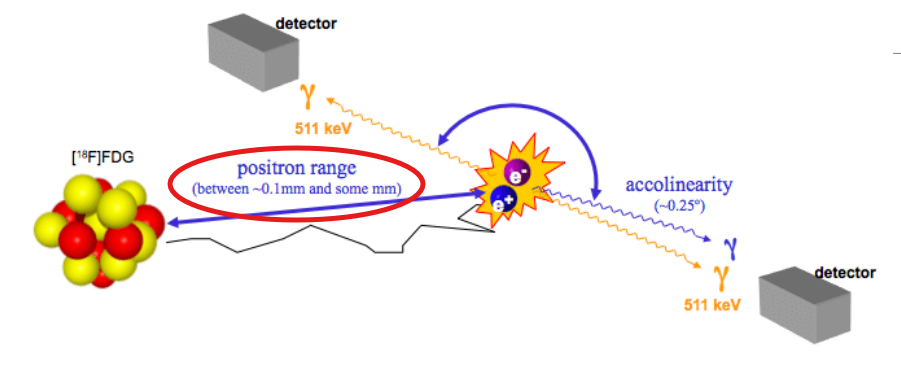

What are the 3 types of errors that PET scanners are associated with?

Error associated with the distance that the positron travels before the annihilation occurs – affects the line of response

Non-colinearity or acolinearity

Elaborate on why there is error associated with PET specific to the distance that the positron travels prior to annihilation

When the positron is made as a byproduct of beta positive decay, it’s ejected from the nucleus and will travel a distance away due to it being high in energy

As a PET camera detects annihilation reactions, every line of response it detects will have around 0.1 mm of error from the range of the positron traveling a distance

Elaborate on how non-colinearity or acolinearity is a source of error for PET

Our detectors in a PET camera work to pick up on two 511 keV photons that are traveling at a straight distance from one another

With non-colinearity, one of the photons will travel at a slight angle (0.25°)

Of the 3 sources of error in PET, which is one that we cannot fix or correct for?

Non-colinearity as this is a source of error that occurs at the origin of the annihilation event